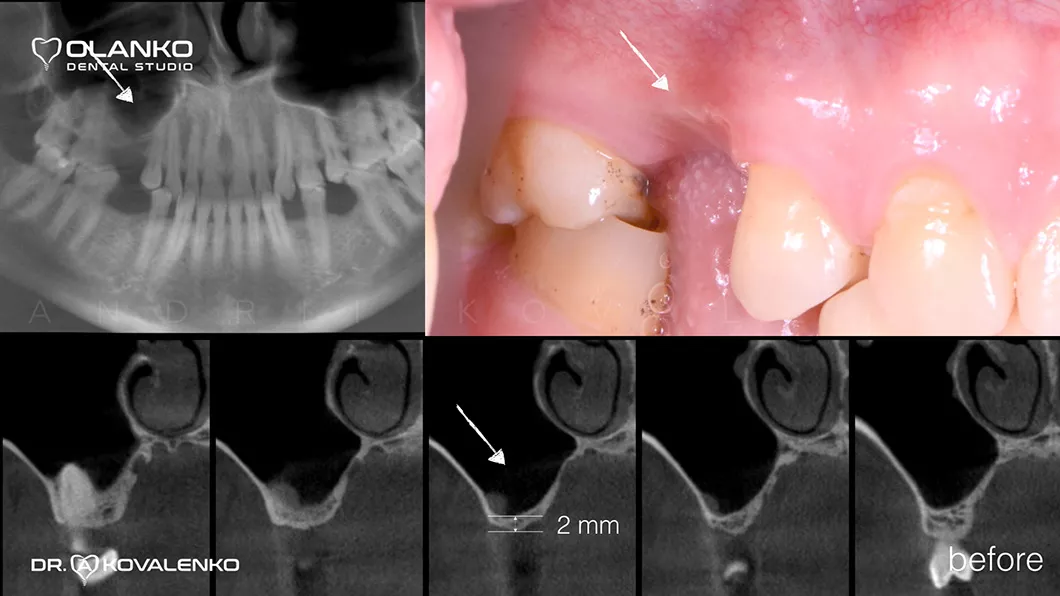

Спеціалісти Olanko dental studio (Оланко) м. Бровари, при виборі методу кісткової пластики, проводять детальний аналіз комп'ютерної томографії та віртуально розставляють положення майбутніх імплантатів в спеціальному програмному забезпеченні IMPLANT STUDIO 3Shape.

Кісткова пластика методом відкритого синус-ліфтингу

*Фотографії з наявністю крові були переведені в чорно-білий формат